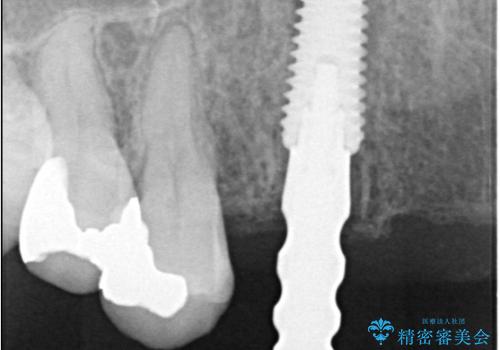

- 歯茎の大きな腫れを主訴に来院された患者様です。前歯5本にはブリッジが装着されていました。レントゲン検査より、右上3番に大きな根尖病巣が認められ、さらに左上1、2番の支台歯にも破折があったため、抜歯を行いました。その後、インプラントを3本埋入し、オールセラミッククラウンのブリッジで補綴しました。

術前のCT画像より、抜歯即時インプラントが可能と判断したため、抜歯と同時にインプラント埋入を行いました。術式にはセミルーナーフラップを用い、唇側の骨吸収を抑える目的でルートメンブレンテクニックを併用しました。